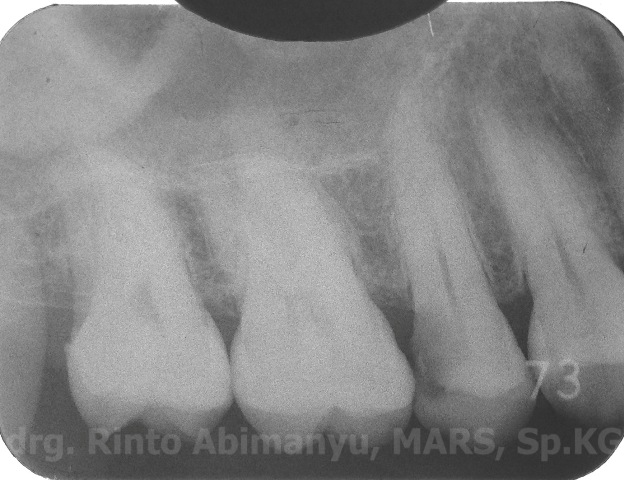

dan ini foto ronsennya…